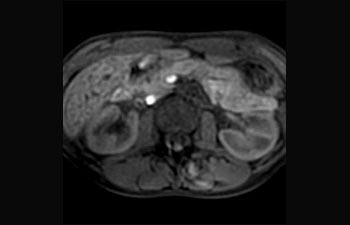

La Sra. Silvia Schiffer, directora y radióloga experta en la clínica Radiologie Schiffer, en Alemania, comparte sus experiencias con el sistema de RM Prodiva 1.5T.

Conozca la opinión de los primeros usuarios de Ingenia Prodiva 1.5T acerca de sus experiencias con el sistema y cómo influye este en su centro de diagnóstico por imagen.

1De acuerdo con un estudio interno en el que se compara el flujo de trabajo con el equipo de RM Achieva. 2 ComforTone estará disponible con Prodiva 1.5T en el cuarto trimestre de 2017 3 De acuerdo con un estudio interno donde se compara el flujo de trabajo en una combinación de aplicaciones cerebrales, musculoesqueléticas, de columna y de cuerpo con el equipo de RM Achieva 4 La operación normal se define como una adquisición típica realizada con suministro continuo de electricidad, así como de refrigeración del imán, sin incluir las actividades de servicio 5 En función del contrato y de la disponibilidad local 6 Con "otros equipos de RM" nos referimos a equipos de RM de 1,5 T de 60 cm para exámenes de cuerpo entero